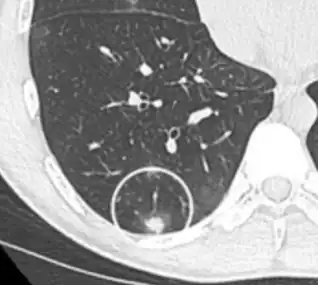

CT image showing patchy areas of ground-glass opacities representing pulmonary edema.

The diffuse pattern typically refers to GGOs in multiple lobes of one or both lungs. Broadly, a diffuse pattern of GGO can be caused by displacement of air with fluid, inflammatory debris, or fibrosis. Cardiogenic pulmonary edema and ARDS are common causes of a fluid-filled lung. Diffuse alveolar hemorrhage is a rarer cause of diffuse GGO seen in some types of vasculitis, autoimmune conditions, and bleeding disorders.[6]